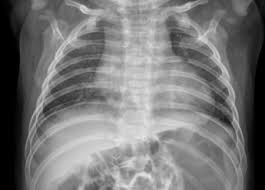

신종인간코로나바이러스 감염 시 나타날 수 있는 대표적인 증상으로는 발열, 기침, 호흡곤란 등이 있습니다. 하지만 초기에는 일반 감기와 유사한 증상이 나타날 수 있어 주의가 필요합니다. 바이러스 감염 여부를 조기에 확인하려면 PCR 검사 또는 신속항원 검사를 활용하는 것이 중요합니다.

특히 신종인간코로나바이러스는 변이 형태로 나타날 수 있어, 면역력이 약한 사람들에게 더욱 위험할 수 있습니다. 감염 여부를 확인하려면 가까운 보건소나 병원을 방문해 검사를 받아보는 것이 좋습니다.